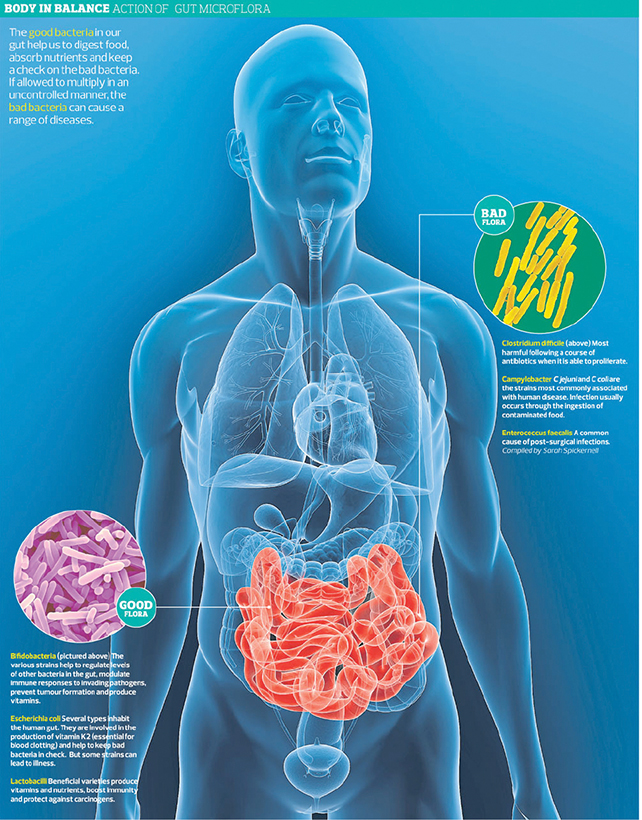

5 Ways Gut Bacteria Affect Your Health

3. IMMUNE SYSTEM

Your gut is the main area in the body where the immune system interacts with what’s brought in from the outside world. Thus, the interaction between gut bacteria and your own cells appear to play an important role in the development of a fully-functioning immune system. According to a 2003 review paper, lymphatic tissue in the intestine contains the largest pool of cells capable of producing an immune response.